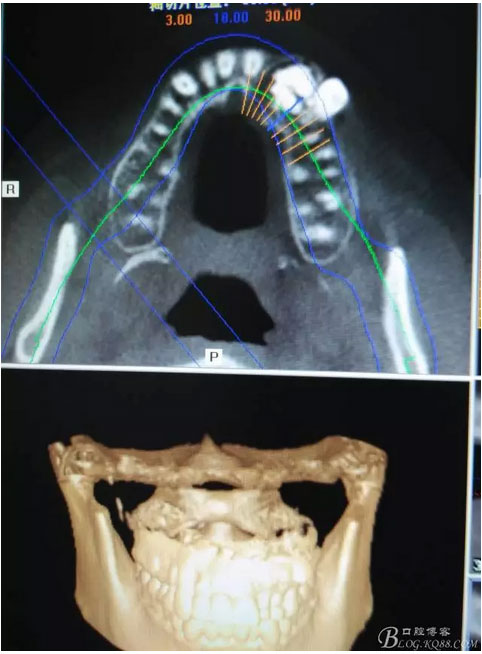

圖1。術前的CBCT影像檢查:22位于鼻底下方,23位于24、25的根方。左側乳Ⅱ、Ⅲ根方顯示囊性改變,囊腔內大量致密鈣化團塊,密度高。